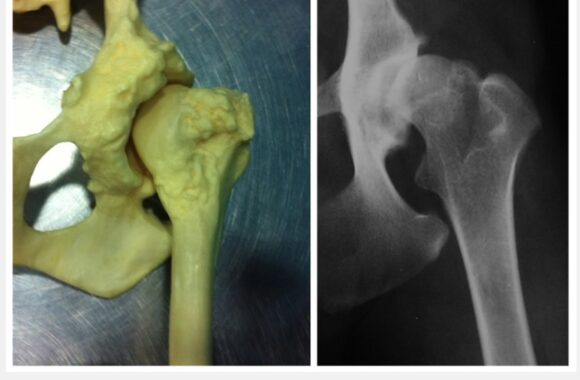

I principali campi d’interesse sono la chirurgia generale e specialistica, l’ortopedia preventiva ed articolare, la traumatologia e la diagnostica per immagini avanzata.

Disponiamo di nuovi locali con avanzate tecnologie ed attrezzature come la TAC VETERINARIA e la RISONANZA MAGNETICA per la diagnostica per Immagini.

Il Servizio Tac Veterinaria a Portici

Attualmente l’unica clinica veterinaria di Napoli e provincia che ha a disposizione una TAC Multistrato da 128 strati in struttura, ultra veloce (total body in meno di 15 sec.), con refertazione in 24h/48h.